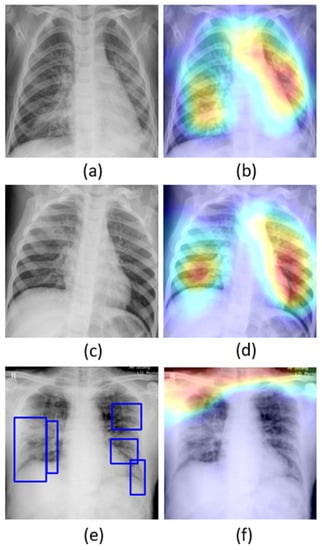

The learned behavior of the baseline-trained VGG-16 model with the pediatric CXR and COVID-19 CXR collections is interpreted through Grad-CAM visualizations and is shown in Figure 5.

The gradients for the bacterial and viral pneumonia classes that are flowing into the deepest convolutional layer of the trained model are used to interpret the neurons involved in the decision-making. The heat maps obtained as a result of weighing these feature maps are superimposed on the original CXRs to identify the salient ROI involved in categorizing the CXRs to their respective classes. It is observed that the model is correctly focusing on the salient ROI for the baseline test data coming from the same training distribution that helps to categorize them into bacterial and viral pneumonia classes. However, the salient ROI involved in categorizing an image from the Montreal-COVID-19 CXR collection that comes from a different distribution compared with the baseline data did not properly overlap with the GT annotations. This further underscores the inference above that the model did not learn the disease manifestations in the aforementioned COVID-19 CXR collections, suggesting that their appearances are distinct.

Figure 5. Original CXRs and their salient ROI visualization: (a,b) show a CXR with bilateral bacterial pneumonia and the corresponding Grad-CAM visualization; (c,d) show a CXR with viral pneumonia manifestations and the corresponding salient ROI visualization; and (e,f) show a sample CXR from the Montreal-COVID-19 CXR collection with ground truth (GT) annotations and corresponding salient ROI visualization. Blue frames in (e) denote radiologist annotations indicating disease regions, which serve as ground truth in our analysis.